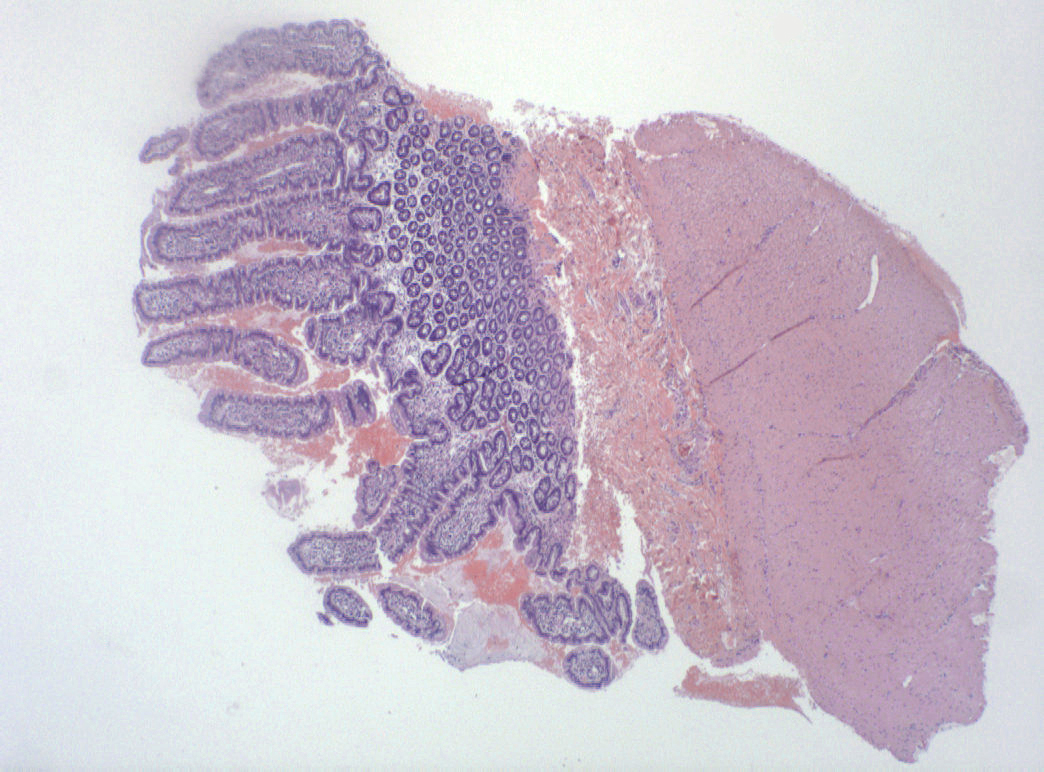

HE-gekleurde coupes van endoscopische duodenum biopten met een lymfo-plasmacellulaire ontsteking (100 x, respectievelijk 200 x). Als gevolg van deze ontsteking zijn zogenaamde cryptabcesjes aanwezig. Dit zijn gedilateerde darmcrypten, die gevuld/overvuld zijn met exsudaat en ontstekingscellen.

HE- gekleurde coupe van een gefixeerd en uitgesneden chirurgisch, "full thickness" biopt van het duodenum. Aan de linkerzijde van de foto is de mucosa aanwezig, aan de rechterzijde de gladde spierlagen en daartussen de submucosa. Deze biopten maken een volledige microscopische beoordeling van alle lagen van de darmwand mogelijk.